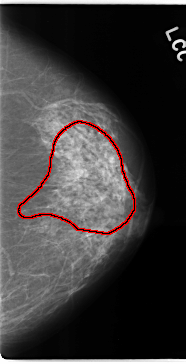

C_0133_1.LEFT_CC

LEFT_CC LINES 4720 PIXELS_PER_LINE 2408 BITS_PER_PIXEL 12 RESOLUTION 50 OVERLAY

FILE: C_0133_1.LEFT_CC.OVERLAY

TOTAL_ABNORMALITIES 1

ABNORMALITY 1

LESION_TYPE CALCIFICATION TYPE AMORPHOUS DISTRIBUTION REGIONAL

ASSESSMENT 4

SUBTLETY 3

PATHOLOGY MALIGNANT

TOTAL_OUTLINES 1

BOUNDARY